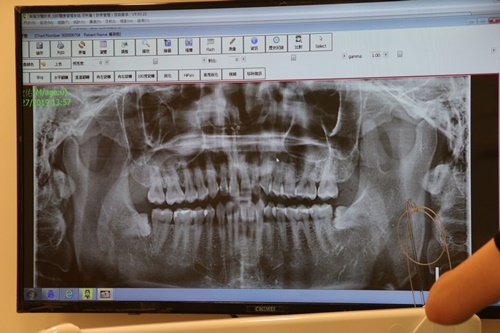

X光片也是很必要的

有X光片矯正醫師才能判斷矯正牙齒移動位置